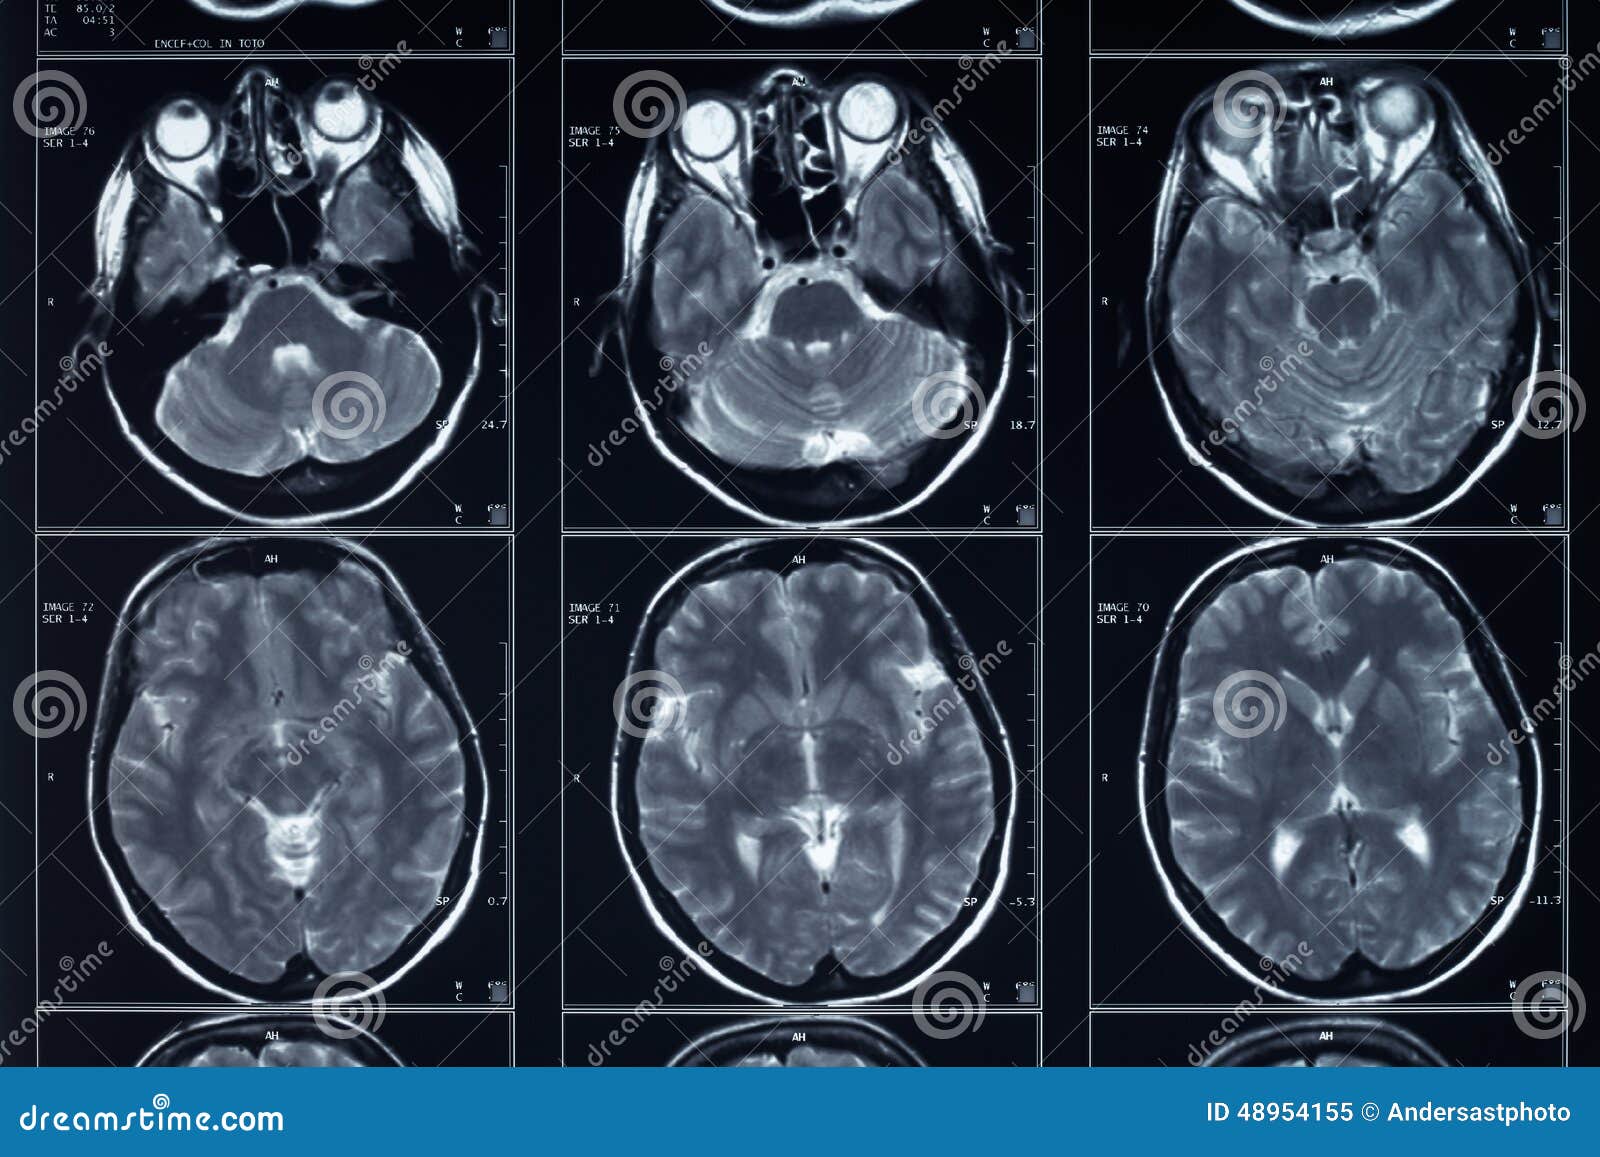

L Imaging Dell Encefalo Tc Ed Rm A Confronto

Risonanza Magnetica Encefalo Medical Imaging Caserta

Risonanza Magnetica Encefalo A Cosa Serve Radiologia Italia

Atlante Di Resonanza Magnetica Del Cervello